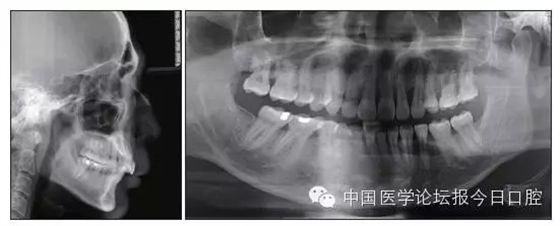

本病例為慢性牙周炎致前牙漂移、深覆(牙合)患者。本病例采用無托槽隱形矯治技術進行治療。無托槽隱形矯治器具有可摘戴、便于口腔衛(wèi)生維護和牙周治療的優(yōu)點,更適合于伴有牙周炎的錯(牙合)畸形患者的治療。 患者男,48歲,前牙有縫、前突求診。 患者面部對稱,側(cè)面觀上頜前突,下頜后縮。 口內(nèi)情況:恒牙列,24、34、44缺失,磨牙Ⅲ類關系,上牙列散隙,上前牙扇形漂移。前牙深覆(牙合)、深覆蓋??谇恍l(wèi)生較差,11與12間牙齦乳頭紅腫,多個牙探診有牙周袋形成,11松動Ⅰ度,余切牙松動(-),患者面像及口內(nèi)像如圖1、2所示。 圖1 治療前面像 圖2 治療前口內(nèi)像 全口曲面體層片(圖3)顯示,患者全牙列牙槽骨吸收;根尖片(圖4)示11近中牙槽骨角形吸收已達根尖1/3,21牙槽骨嵴頂吸收至根1/2,23牙槽骨近中骨板角形吸收至根1/2。磨牙區(qū)骨嵴頂吸收3mm。治療前頭顱側(cè)位片見圖3,治療前ODS模型見圖5。 圖4 治療前根尖片 圖5 治療前ODS模型 牙型:安氏Ⅲ類。骨型:Ⅱ類。面型:上頜前突,下頜后縮。 問題列表為:①上牙列間隙;②上切牙病理性牙移位;③前牙深覆(牙合)、深覆蓋;④24、34、44缺失;⑤慢性牙周炎。 矯治目標包括:①排齊牙列,關閉牙列間隙;②改善前牙深覆(牙合)、深覆蓋;③改善牙周狀況。 矯治設計有:①牙周基礎治療與維護。②壓低、內(nèi)收上切牙,關閉上牙列間隙。③壓低下切牙,伸長下后牙,整平Spee曲線,改善前牙覆(牙合)、覆蓋。 患者進行全口齦上潔治、齦下刮治,口腔衛(wèi)生宣教,并按牙周醫(yī)師的要求,每2~3個月行牙周檢查與治療。 牙周基礎治療結(jié)束3個月,開始隱形矯治。于14、25、35、36、45、46上粘接附件(圖6),于16、26(牙合)面粘接(牙合)墊。 圖6 ODS設計附件粘接圖示 矯治過程中注意(牙合)墊是否脫落或磨損,及時修補。 注意上前牙內(nèi)收時有無咬合干擾,及時調(diào)(牙合)。下頜前磨牙伸長到位后,磨除16、26(牙合)墊。 下頜佩戴第24步矯治器時,分別在36、37、46、47的頰、舌側(cè)粘接舌扣,矯治器上預留伸長空間,用3/16英寸、3.5盎司皮圈牽引,輔助伸長下磨牙(圖7)。 患者共戴用矯治器上頜32步,下頜26步。 矯治后,牙列間隙關閉,面型及覆(牙合)覆蓋改善。11根尖片(圖8)顯示,治療后較治療前,牙周支持組織增加,牙槽骨角形吸收區(qū)水平向縮小0.3mm,垂直向縮小0.6mm。11松動Ⅰ度,余切牙無松動。 圖8 治療后根尖片 圖9 治療后口內(nèi)像 圖10 治療后X線檢查 圖11 治療后ODS模型 正畸-牙周聯(lián)合治療對于牙周組織的影響 多學科綜合治療牙周炎患者不再是正畸治療的禁忌證。良好的牙周治療為正畸治療中的牙齒移動打下堅實基礎,而正畸治療排齊牙齒、去除(牙合)干擾,有利于牙周健康。 牙周炎患者的正畸治療必須在牙周炎癥得到控制后才能進行,否則,菌斑會隨著牙齒的移動,特別是壓低而使牙周炎癥加重。牙周炎的正確診斷、牙周炎癥控制、正畸治療中和治療后的認真維護是治療成功的關鍵。根據(jù)臨床需要,一般每2~4周做一次潔治,每3個月進行牙周評估,同時患者必須進行非常良好的日??谇恍l(wèi)生維護。 固定矯治器使得牙周檢查、潔治和日??谇恍l(wèi)生維護變得困難,隱形矯治器可自行摘戴,便于患者日常維護和牙周治療,節(jié)約時間,提高菌斑控制效果。 有臨床研究表明,對于存在(牙合)創(chuàng)傷,伴有角形吸收的患牙,經(jīng)過牙周翻瓣手術控制住牙周炎癥后,使用正畸輕力壓低患牙,可以改善牙槽骨吸收的程度,并獲得一定程度的牙周新附著。本病例切牙壓低后,原來的牙槽骨吸收有改善。 病理性牙移位 病理性牙移位(PTM)在重度牙周炎患者中的發(fā)生率為30%~50%,且常見于上前牙區(qū)。其主要由于牙周支持組織喪失尤其是骨組織的丟失,咬合因素(如后牙缺失、前牙深覆牙合、牙合創(chuàng)傷等),頰舌唇肌力量不平衡及牙周和根尖周組織炎癥所致,是牙周炎患者要求正畸治療的主要原因之一。 PTM須通過正畸、牙周聯(lián)合,有時須配合修復才能達到理想的治療效果。正畸治療通常是壓低牙齒,臨床研究表明,牙周手術配合正畸壓低可以產(chǎn)生新附著,有利于PTM牙周組織的恢復。 本病例右上中切牙牙槽骨角形吸收,在盡量保證治療前后根尖片投照角度一致的情況下,以鄰牙作為校準,在根尖片上對治療前后的骨量進行評價,治療后牙槽骨角形吸收區(qū)水平向縮小0.3 mm,垂直向縮小0.6mm。盡管根尖片并不能說明骨量改變,但從影像學上能看到骨吸收區(qū)域有所減小。 無托槽隱形矯治器矯治牙周病的優(yōu)勢 無托槽隱形矯治器具有可摘戴、便于口腔衛(wèi)生維護和牙周治療的優(yōu)點,更適合于伴有牙周炎的錯(牙合)患者的治療;同時,無托槽隱形矯治器佩戴后具有牙弓夾板和(牙合)板的作用,可有效減少側(cè)向力,有利于牙周的恢復和減輕牙齒松動;由于無托槽隱形矯治器的設計是在三維數(shù)字模型上進行的,每個矯治器移動牙齒的數(shù)量和每個牙齒的移動距離可以得到量化控制,因而可以根據(jù)患者牙槽骨水平和對矯治力的耐受情況個性化設計矯治力,并且可以根據(jù)矯治中牙齒移動情況調(diào)整后續(xù)矯治器的設計。 有關磨牙伸長 單純使用無托槽隱形矯治器同步伸長后牙比較困難。該病例先使用磨牙(牙合)墊打開咬合,通過矯治器伸長前磨牙,在前磨牙建立咬合后,磨除磨牙上的(牙合)墊,通過輔助牽引伸長磨牙,最終達到伸長后牙、整平Spee曲線的目的。 史真,主任醫(yī)師,現(xiàn)任北京黃寺整形外科醫(yī)院口腔科主任,第四軍醫(yī)大學口腔正畸學碩士,為世界正畸醫(yī)師聯(lián)盟(WFO)會員、全軍口腔醫(yī)學專業(yè)委員會委員、中華口腔正畸專業(yè)委員會委員、中華醫(yī)學美學與美容學會齒科美容學組成員、北京口腔醫(yī)學會兒童口腔專業(yè)委員會常務委員、北京口腔醫(yī)學會正畸專業(yè)委員會委員、《中華醫(yī)學美學與美容》雜志審稿專家,是我國最早開展無托槽隱形矯治技術的口腔醫(yī)師之一。

圖3 治療前頭顱側(cè)位片及曲面體層片